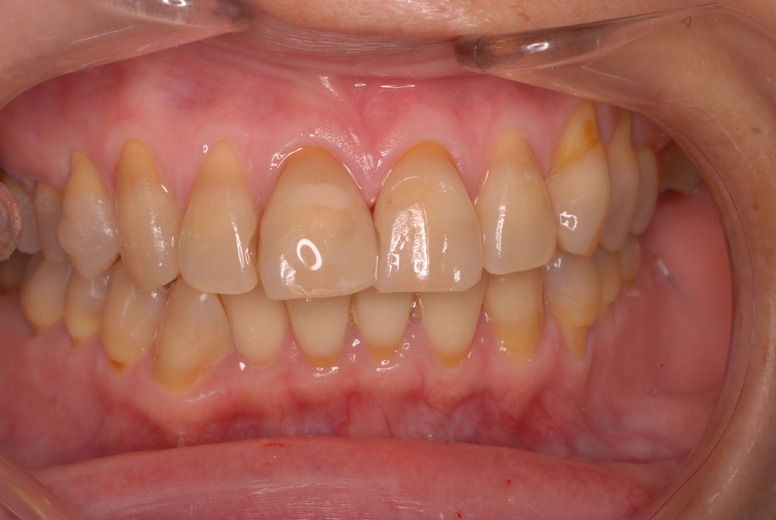

歯周病の疑いで東京のかなり遠方の方が来院されました。

驚くべきことですが、定期検診は受けていたそうです。しかしながら歯周病の指摘は受けたことがないそうです。

何故か?定期検診が虫歯のチェックのみになり、又肝心の歯周病の検査や歯周病の部分の予防や治療のためのブラシの使い方などを学んだ事がないのです。

本当に患者さんのことを考えると憂鬱になります。歯周病が悪化すると殆ど回復は無理だからです。